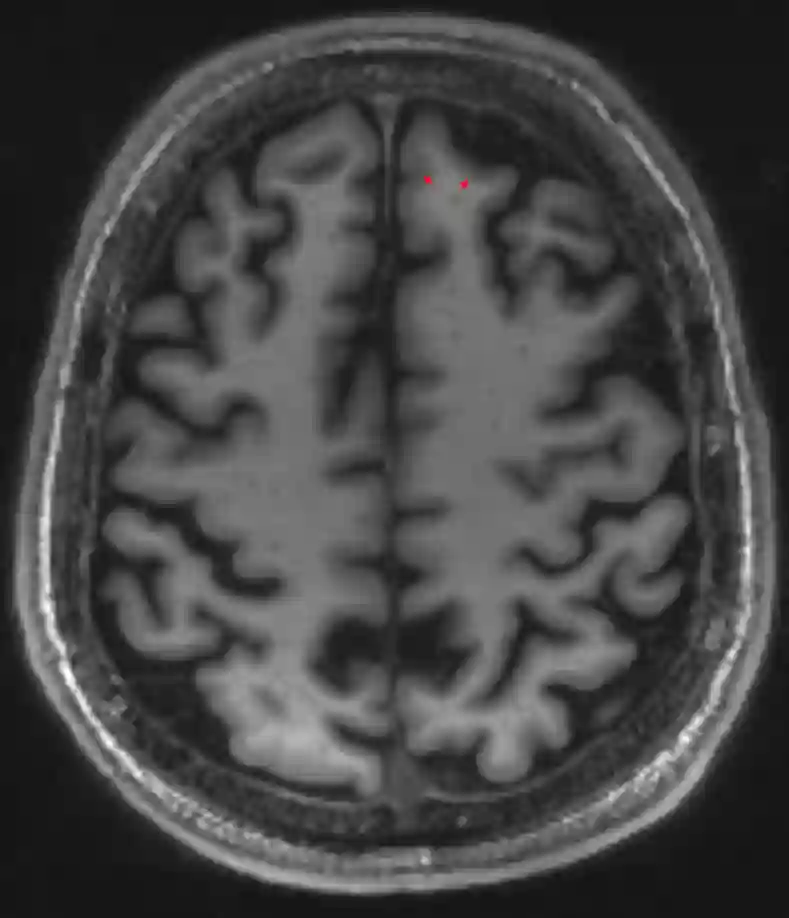

Im Gehirn und Rückenmark wird zwischen der grauen Substanz (Substantia grisea) und der weißen Substanz (Substantia alba) unterschieden. In der grauen Substanz befinden sich die Zellkörper, welche auch Perikarya genannt werden.

Graue Substanz MRI

Graue Substanz (beispielsweise markiert mit zwei roten Pfeilen) im Gehirn in einer axialen MDEFT MRI Sequenz.